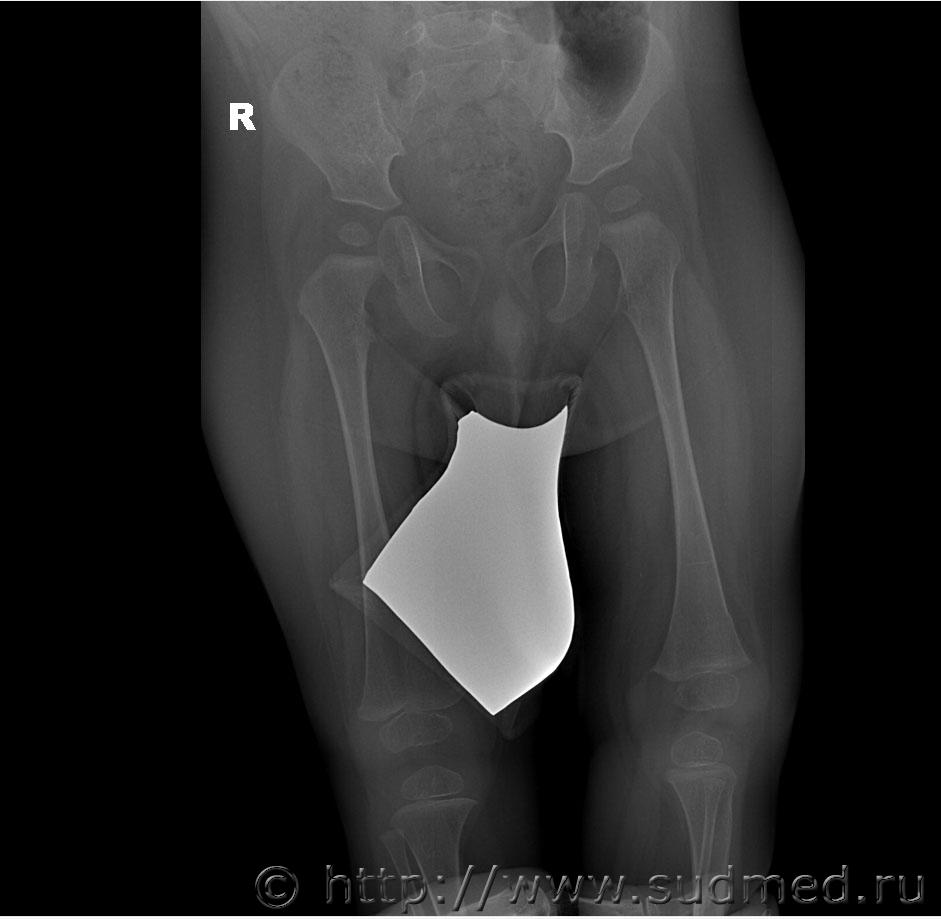

Добрый день, уважаемые коллеги. Нужна помощь в оценке степени тяжести поднадкостничного перелома нижней трети диафиза бедренной кости у ребенка 1 года. Судя по снимкам, перелом вколоченный. По версии следствия, перелом образовался во время массажа, ребенок лежал на животе, со слов массажиста в момент упора ребенка стопами в ладонь врача, при движении вперед в горизонтальном положении ребенок заплакал. В вертикальном положении при упоре стопами в пеленальный стол стал приподнимать больную ногу и плакать. снимки выполнены в тот же день. Рентгенолог изменений структуры кости на снимке не отмечает.

Я рентгенолог не профессиональный и не детский, но перелома не вижу. Ограниченное тяжистое или симметрично-очаговое вспучивание компакты (отторжение надкостницы?) в супракондилярных зонах - местах крепления мышц голени.

Перелом есть. По типу "зеленой веточки", судя по симметричности, действительно вколоченный.

Да. По формальному признаку: перелом диафиза бедренной кости. Легкий или средний вред Мед.критериями всерьез не обосновать.

Это те же снимки, не обрезанные.

Судебная медицина - Прикрепленное изображение Судебная медицина - Прикрепленное изображение

Честно говоря, какого -либо уплотнения губчатого вещества я тоже не вижу, возможно Вы правы по поводу отторжения надкостницы. Но две консультации рентгенологов указывают на перелом. Думаю нужна консультация снимков детским травматологом-ортопедом с привлечением рентгенолога.